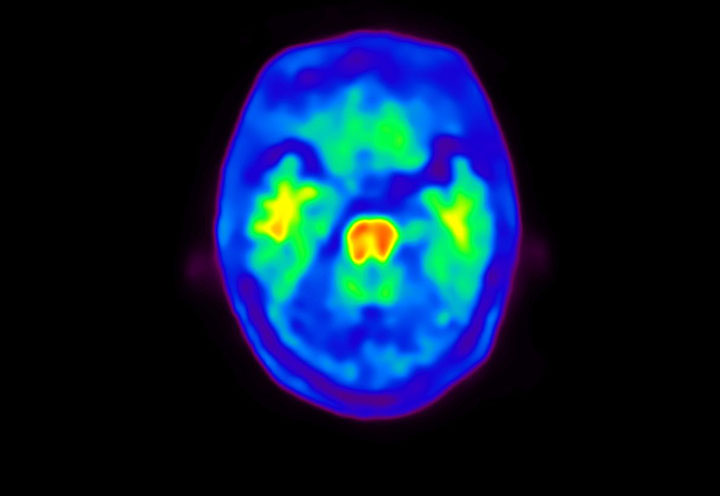

Head / Case4 : Amyloid

Courtesy : Kindai University Hospital

- Imaging protocol

- Injected dose: 3.21 MBq/kg, 18F-Flutemetamol

- Uptake time: 100 minutes

- Scan time: 20 minutes